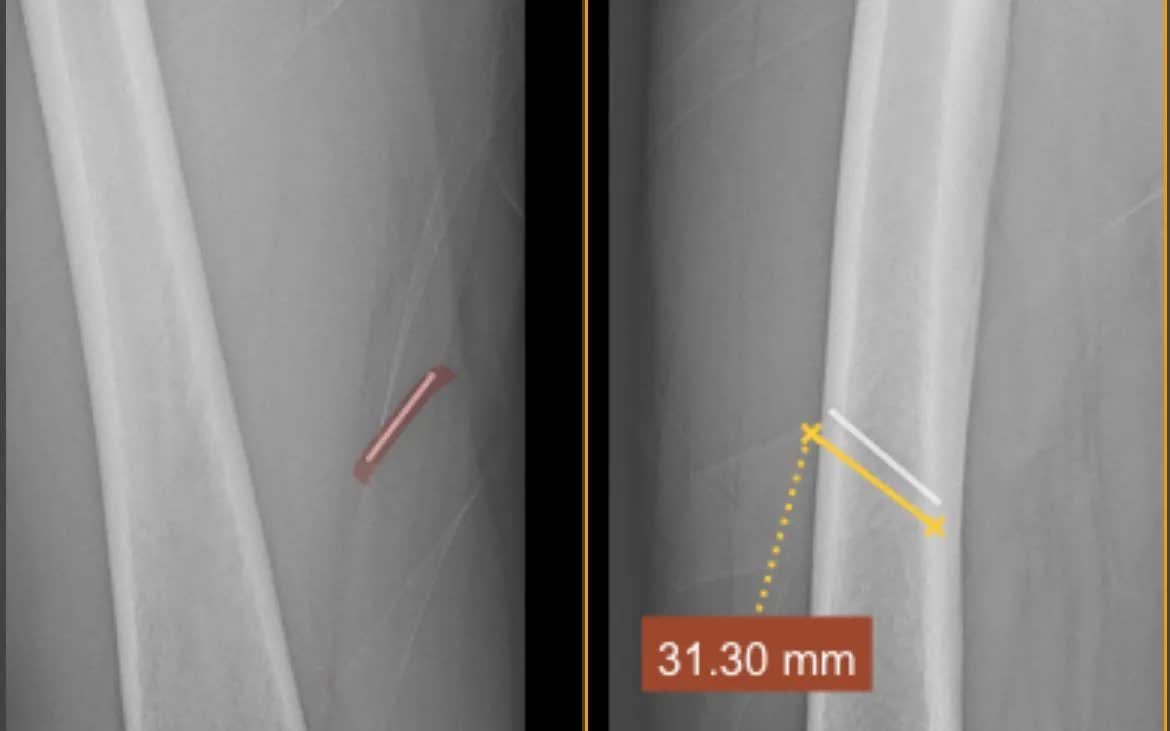

Một bệnh nhân bị tai nạn lao động, dị vật kim loại nằm sâu trong tổ chức phần mềm đùi đã được các bác sĩ Trung tâm Y tế Quế Võ (Bắc Ninh) xử trí kịp thời, đảm bảo an toàn.

Bệnh nhân nam, 63 tuổi, làm nghề thợ mộc. Trong quá trình lao động, bệnh nhân không may bị súng bắn đinh bắn một chiếc đinh kim loại vào mặt trong đùi. Dị vật nằm sâu trong tổ chức mỡ và cơ, tiềm ẩn nguy cơ tổn thương mô mềm, nhiễm trùng và biến chứng nếu không được xử trí đúng cách.

Ngay sau khi tiếp nhận, các bác sĩ đã khai thác bệnh sử, thăm khám lâm sàng và chỉ định các phương tiện chẩn đoán hình ảnh nhằm xác định chính xác vị trí, độ sâu và hướng đi của dị vật. Trên cơ sở đó, ekip Khoa Ngoại tiến hành thủ thuật lấy dị vật với sự hỗ trợ của trang thiết bị chuyên môn.

Quá trình can thiệp được thực hiện thận trọng, đảm bảo hạn chế tối đa tổn thương mô xung quanh. Dị vật kim loại đã được lấy ra an toàn khỏi tổ chức phần mềm. Sau thủ thuật, tình trạng bệnh nhân ổn định, không ghi nhận biến chứng, tiếp tục được theo dõi và chăm sóc theo đúng quy trình chuyên môn.